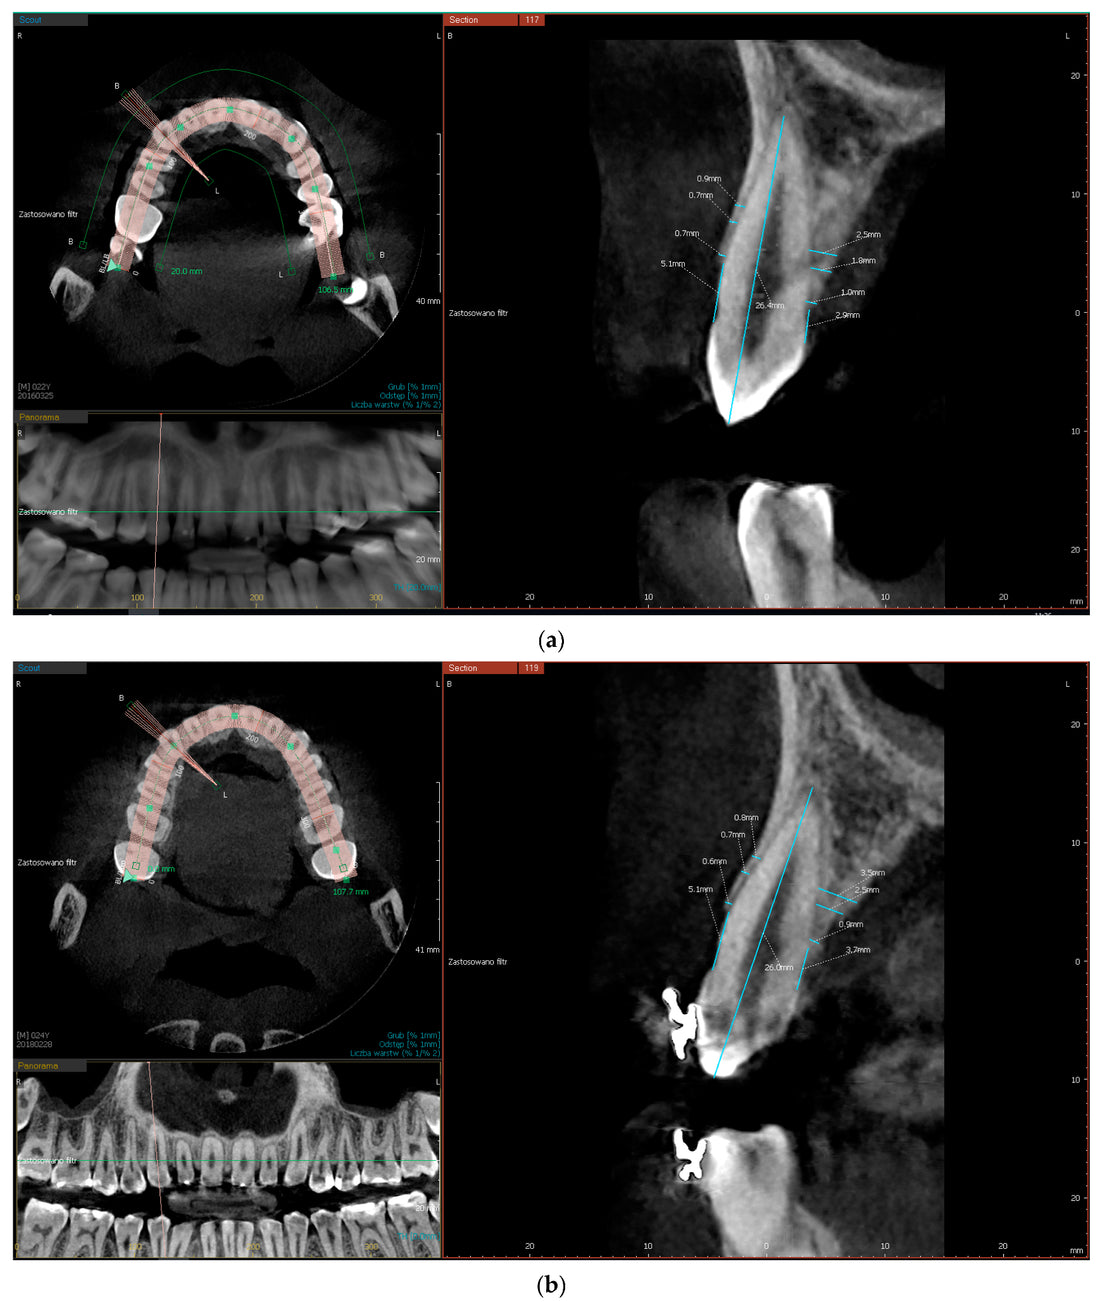

Dominance of Dental Applications: CBCT systems are predominantly used in dentistry in Germany, with a strong focus on dental implantology, orthodontics, and endodontics. The ability to obtain 3D imaging of teeth, jawbones, and surrounding tissues makes CBCT invaluable for accurate diagnosis and treatment planning in dental practices.

Technological Advancements: German dental and medical practices are increasingly adopting advanced CBCT systems with improved image resolution, lower radiation doses, and enhanced software for 3D imaging and analysis. These advancements are key drivers for the adoption of CBCT technology in both diagnostic and surgical procedures.

Orthodontics and Implantology Growth: Germany is seeing a rise in the number of adults seeking orthodontic treatments, as well as an increasing demand for dental implants. CBCT’s ability to precisely assess bone structure and aid in the planning of these treatments has bolstered its demand in the German market.